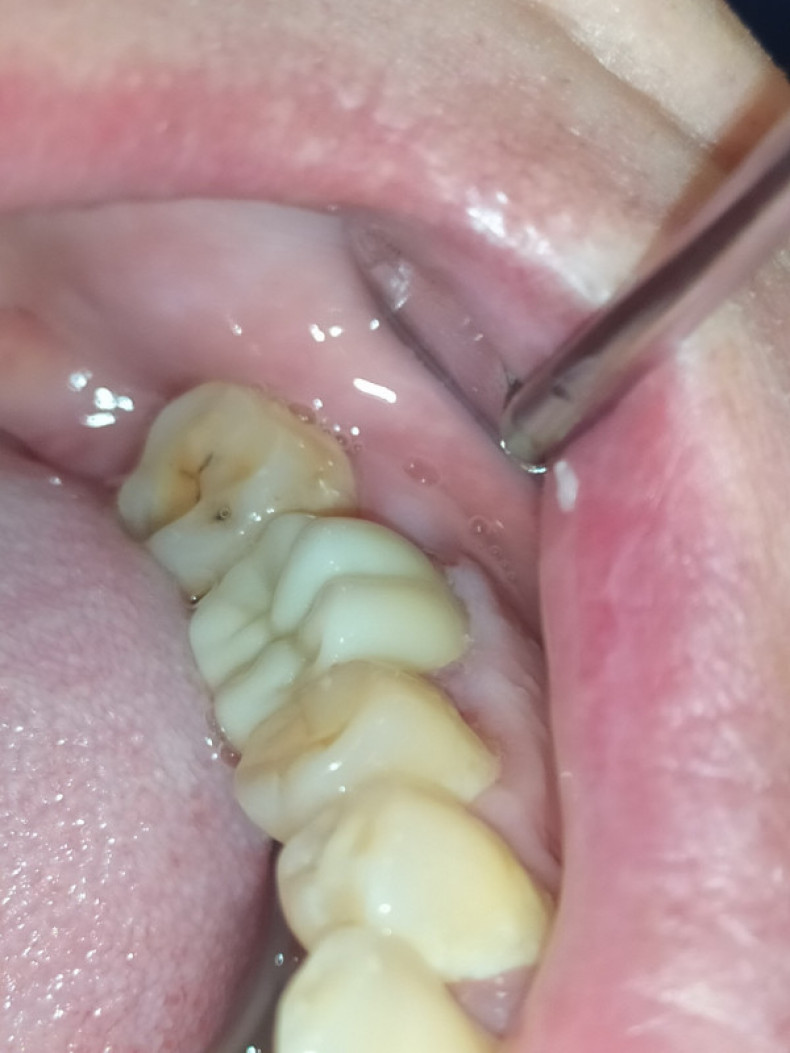

Чистка зубів від каменю у Львові

Видалення зубного каменю запобігає запаленню ясен і розвитку карієсу. Тут зібрані пропозиції від стоматологічних клінік і фахівців, які виконують процедури з видалення твердих відкладень.